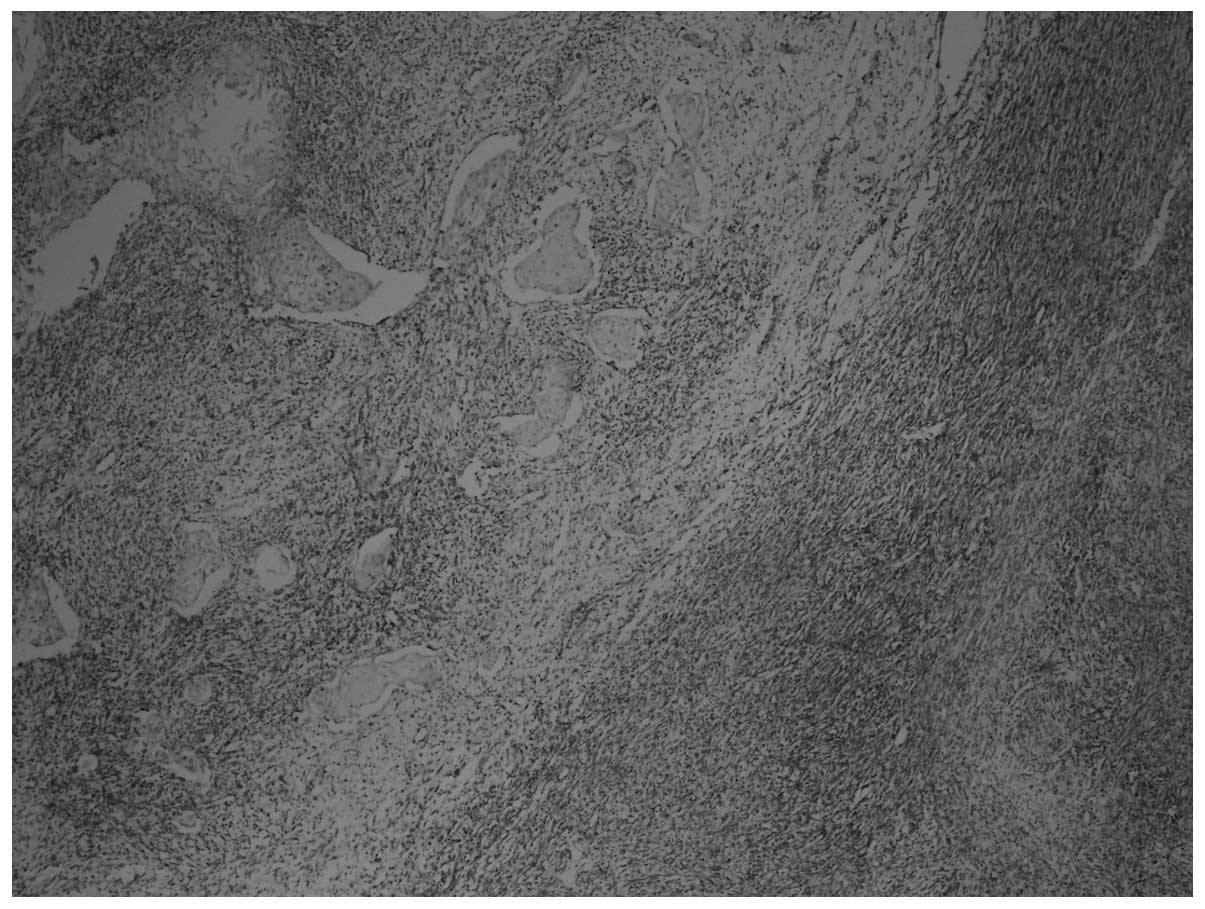

On immunohistochemical examination, the tumor cells were pan-cytokeratin+, DKA+, desmin+, vimentin+, CD117−, CD34− and S-100− (Figs. 3 and 4). The Ki-67 proliferation index was 70%. Sarcomatous components were identified, together with carcinomatous components and transitional zones between the two. The transitional zones between sarcomatous and carcinomatous areas are demonstrated in Figs. 3 and 4, using pan-cytokeratin and vimentin immunostaining, respectively.

Figure 3

Immunohistochemical staining with pan-cytokeratin showing cytokeratin-negative sarcomatous areas on the left and cytokeratin-positive carcinomatous areas on the right (magnification, x40).